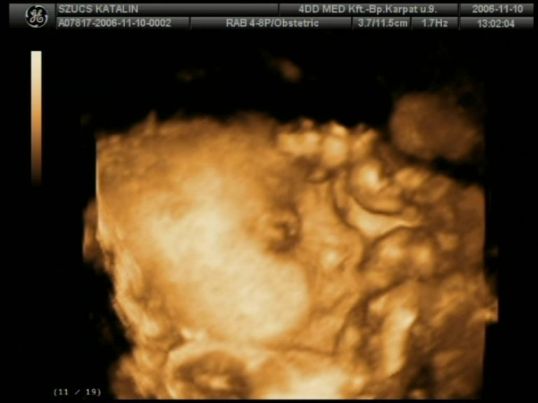

Tegnap voltunk UH-n, Pöttyöm 2,3 cm ülömagasságu, és megint integetett